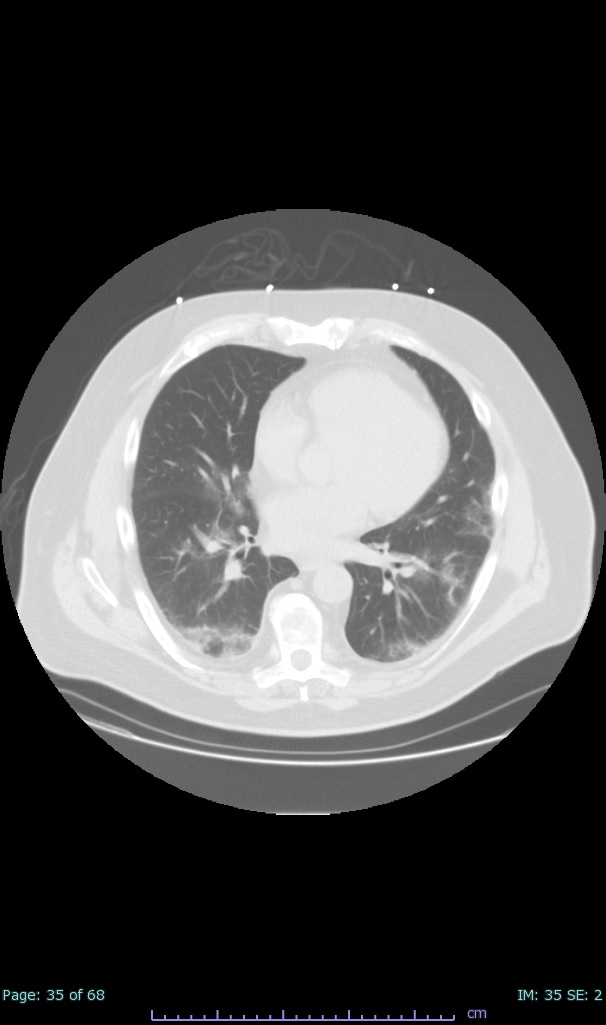

- 100% subpleural involvement, 33% + centrolobular involvement

- 40% even apical/basilar, 27% basilar dom, 5% mid dom. 1/17

- 66% had some + CXR finding I could correlate to a CT finding

- 66% had documented exposure, rest I couldn't find either way